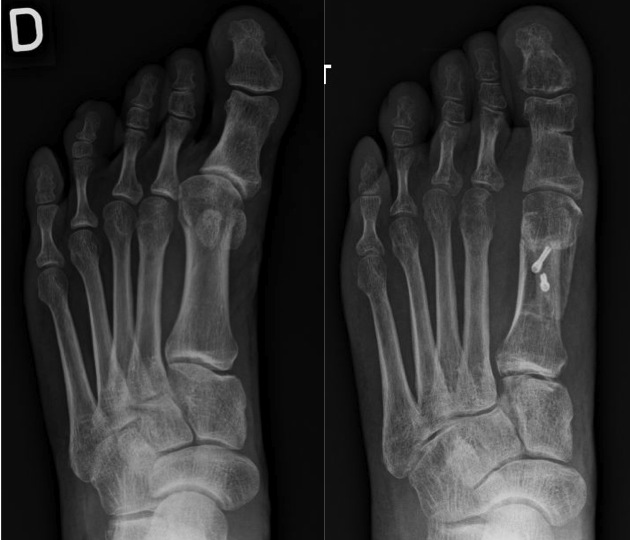

Généralement, un hallux varus survient dans les suites d’une opération pour un hallux valgus, et est de fait une complication due à un excès de correction. D’autres causes sont cependant possibles : post-traumatiques, en association à certaines maladies systémiques inflammatoires comme la polyarthrite rhumatoïde ou le psoriasis, quelques cas sont congénitaux…

Si cette déformation est peu gênante et si la déformation reste souple, vous pouvez simplement porter des chaussures à bouts larges ce qui limite le frottement. Si la déformation et la raideur augmentent, les chaussures adaptées ne suffissent plus. On peut alors proposer une solution chirurgicale. Il faut préalablement vérifier la mobilité et la réductibilité de l’articulation métatarsophalangienne. Si elle est raide et douloureuse, la meilleure solution est alors l’arthrodèse.